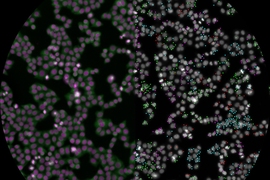

Now, researchers at the Broad Institute and the National Emerging Infectious Diseases Laboratories (NEIDL) at Boston University have used an image-based screening method developed at the Broad to identify human genes that, when silenced, impair the Ebola virus’s ability to infect. The method, known as optical pooled screening (OPS), enabled the scientists to test, in about 40 million CRISPR-perturbed human cells, how silencing each gene in the human genome affects virus replication.

Using machine-learning-based analyses of images of perturbed cells, they identified multiple host proteins involved in various stages of Ebola infection that when suppressed crippled the ability of the virus to replicate. Those viral regulators could represent avenues to one day intervene therapeutically and reduce the severity of disease in people already infected with the virus. The approach could be used to explore the role of various proteins during infection with other pathogens, as a way to find new drugs for hard-to-treat infections.

The team used CRISPR to knock out each gene in the human genome, one at a time, in nearly 40 million human cells, and then infected each cell with Ebola virus. They next fixed those cells in place in laboratory dishes and inactivated them, so that the remaining processing could occur outside of the high-containment lab.

After taking images of the cells, they measured overall viral protein and RNA in each cell using the CellProfiler image analysis software, and to get even more information from the images, they turned to AI. With help from team members in the Eric and Wendy Schmidt Center at the Broad, led by study co-author and Broad core faculty member Caroline Uhler, they used a deep learning model to automatically determine the stage of Ebola infection for each single cell. The model was able to make subtle distinctions between stages of infection in a high-throughput way that wasn’t possible using prior methods.

By sequencing parts of the CRISPR guide RNA in all 40 million cells individually, the researchers determined which human gene had been silenced in each cell, indicating which host proteins (and potential viral regulators) were targeted. The analysis revealed hundreds of host proteins that, when silenced, altered overall infection level, including many required for viral entry into the cell.